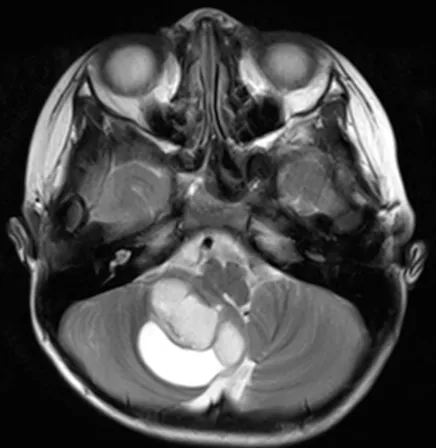

体格检查显示步态共济失调明显,左侧面部V2和V3分布区感觉明显...

这台手术由巴特朗菲教授主刀。虽然病灶周围紧邻面听神经、三...